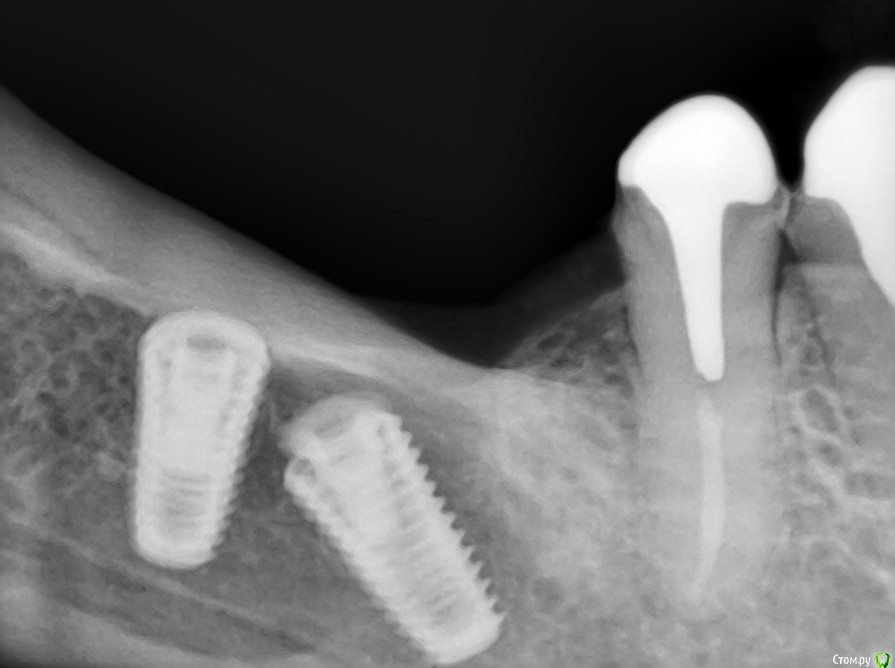

kriokov Опубликовано 16 июля, 2016 Поделиться Опубликовано 16 июля, 2016 Найду залью скрины кт до и прицельный снимок после фиаско 3 Ссылка на комментарий

kamranchick Опубликовано 18 июля, 2016 Автор Поделиться Опубликовано 18 июля, 2016 Снимок экрана (7).jpgав.jpgВ итоге что сделали? Ссылка на комментарий

kriokov Опубликовано 18 июля, 2016 Поделиться Опубликовано 18 июля, 2016 В итоге что сделали?убрал болтающийся в костной полости медиальный имплантат. Для этого пришлось чуть расширить вход крестально трепаном, Дефект подвергся ревизии , но не до изумления ( до более - менее плотных стенок), за дистальным болтом сребком забрана ауто внесена в дефект, сверху мембрана тмо (что было). Через 2 месяца буду по новой в этой зоне болт вкручивать. Ччто выйдет - по факту отпишусь. Ссылка на комментарий